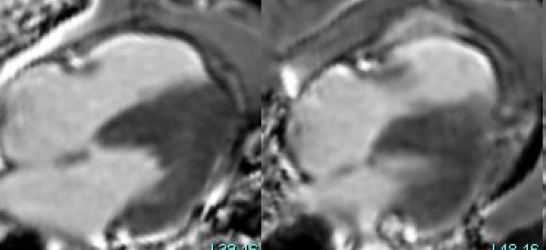

Isolated RV infarction.